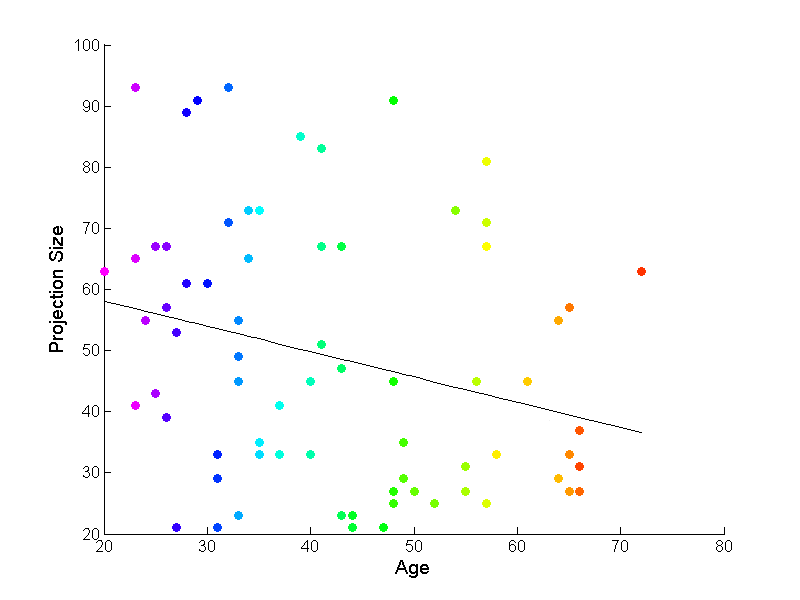

This data analysis has been conducted by running the WO+S method, since this one consistently gave the best results in our simulation. Each data point is projected onto the resulting best fitting tree-curve. Figure 6 shows an example of the relation between the size of this projection with the age of each subject. The black line was fitted to the data using linear regression. This plot was created for all of the sub-populations available, but this one is quite representative, so others are not shown to save space.

The tree-curve tool yields significant slope -values for all of the sub-populations available in this data set. These are summarized in Table 3. The table contains the slope p-values obtained using the first principal -tree-lines in Section 3.4, and the first principal -tree-lines in Aydın et al. (2009). These results, together with further comparisons done using different versions of the brain artery data set and different correspondences can be found in Aydın (2009) (see Tables , , and ). These strongly significant results obtained using tree-curves prove that this mode of analysis is a powerful tool to explain variation in binary trees.

In addition, as shown in Figure 6, the very high projection sizes obtained renders this tool of analysis an attractive option. The first principal tree-curve captures of the nodes that exist in the data sets. This ratio again well exceeds what was obtained by the first principal -tree-line () and the first principal -tree-line (). In fact, Aydın et al. (2009) reports a coverage obtained by combining the first principal component -tree-lines for descendant correspondence in their Figure . The ability to summarize larger portions of data with the first principal component is a valuable contribution of tree-curves.